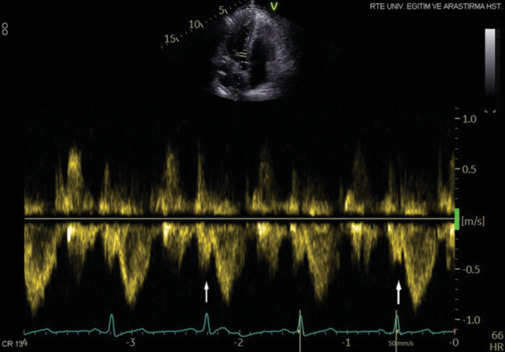

Objective: Ankylosing spondylitis (AS) is a persistent inflammatory disease affecting the axial skeleton which may lead to cardiovascular involvement. We examined the relationship between the presystolic wave (PW), which is frequently encountered in the evaluation of the left ventricular (LV) outflow tract, and AS.

Results: Patients were categorized into two groups: patients diagnosed with AS (n = 64) and patients without AS (n = 53). LV ejection fraction (P = 0.014), LV mass index (P < 0.001), mitral E wave velocity (P = 0.002), and PW (P = 0.014) were independently linked with AS.

Conclusion: A substantial correlation was found between PW and AS.